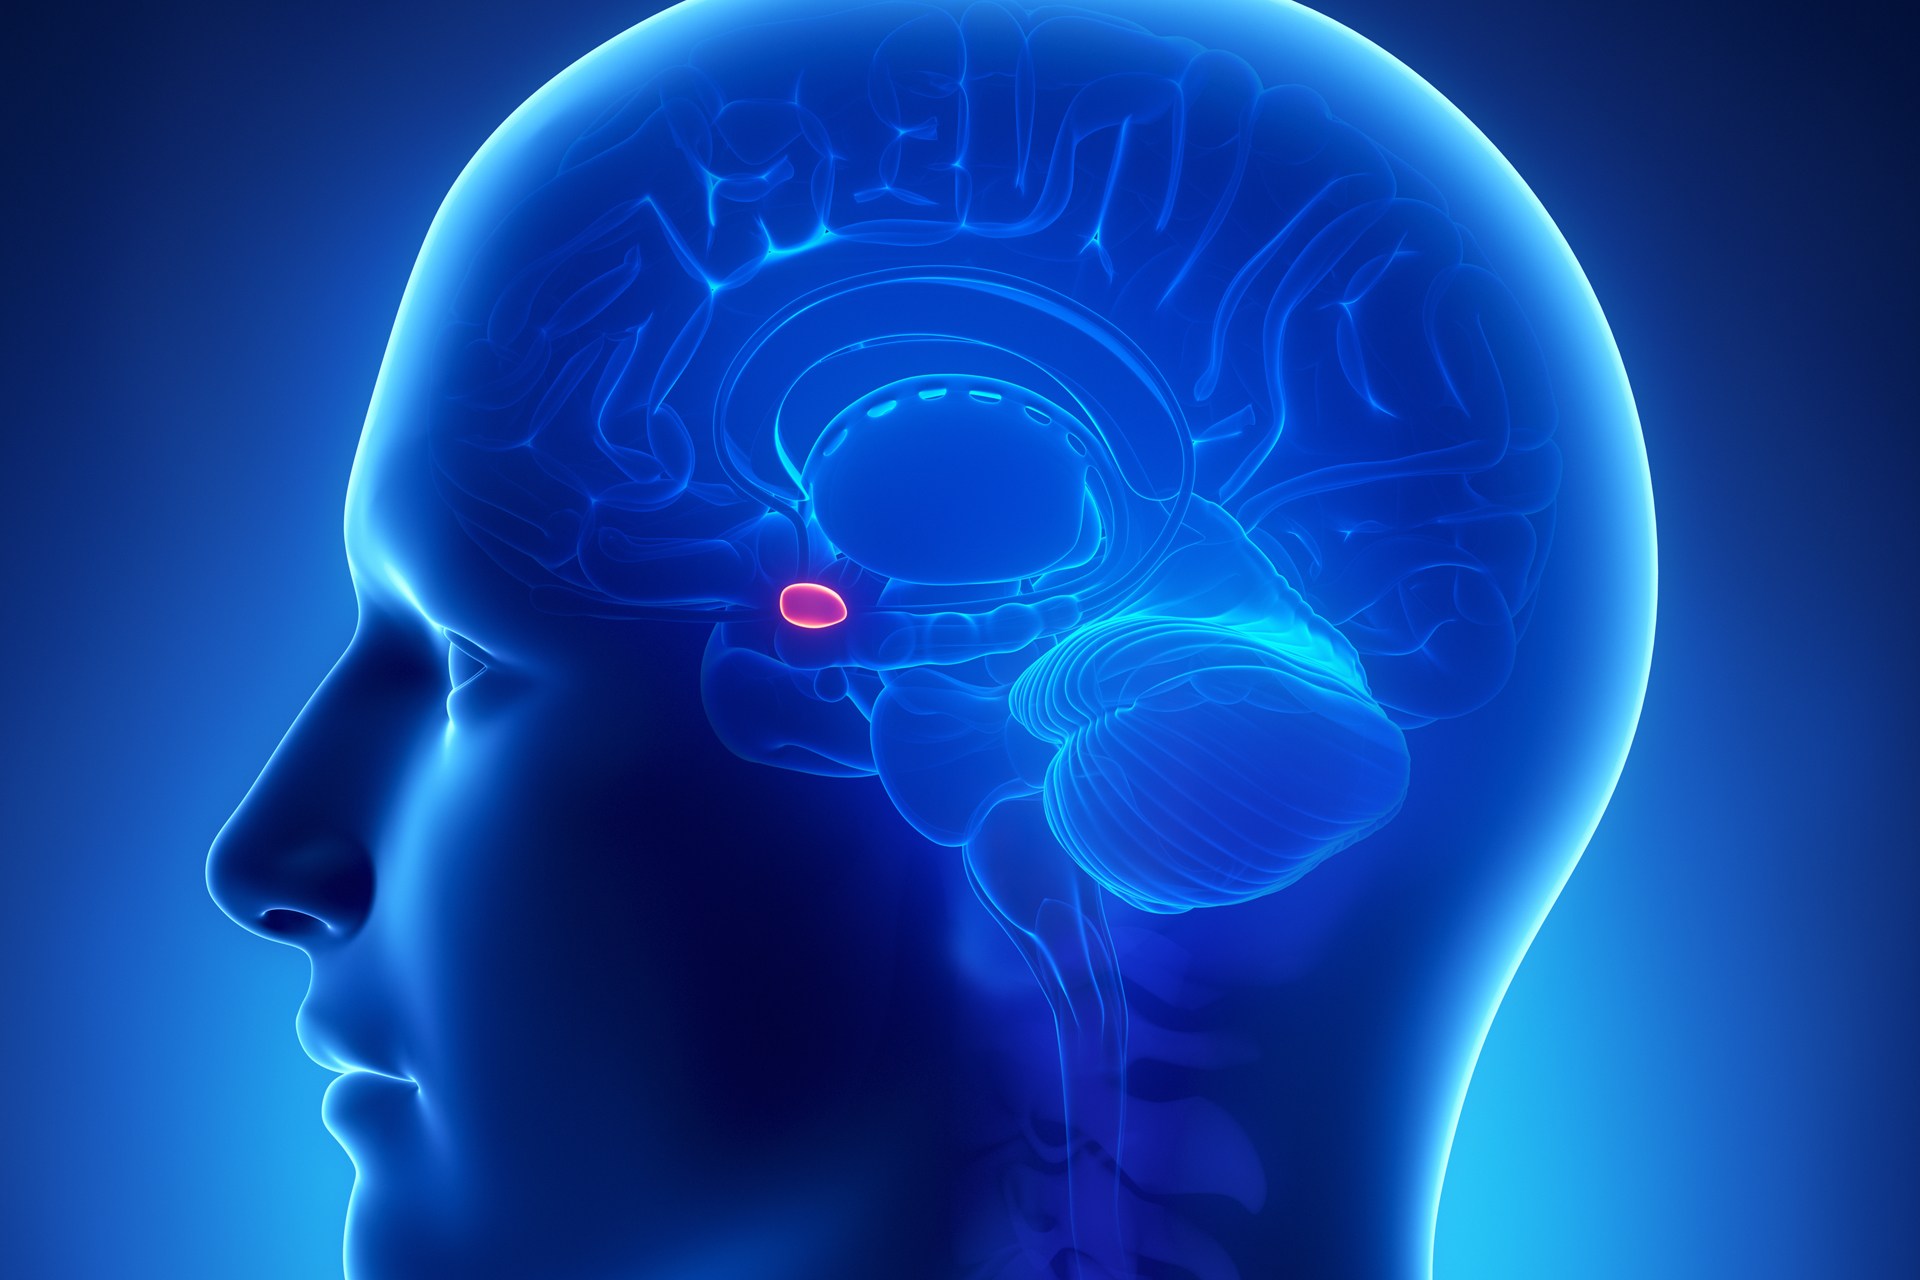

Amygdala: What It Is and What It Controls

Know Your Brain: Amygdala

Damage to the Amygdala: Functions, Symptoms, & Treatments

Amygdala Function and Location

Amygdala's Location and Function

Amygdala - The Science of Psychotherapy

Amygdala: Anatomy, Location, and Function

Schematic drawing illustrating the location of the amygdala and